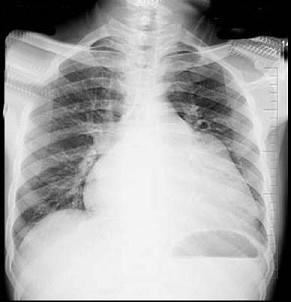

问题 56岁男性患者,劳累后心慌气促10余年,近来自觉症状加重。临床听诊,心尖区有舒张期隆隆样杂音,行胸部X检查,如图所示,你认为下列描述正确的是 ( )

选项 A、考虑三尖瓣狭窄 B、考虑二尖瓣狭窄 C、右前斜位示左心房增大,心后上缘后突压迫冲钡食管 D、左前斜位示心影向后下方突出 E、后前位示双侧肺血增多,肺动脉段隆起,左心缘出现第3弓

答案 BCDE